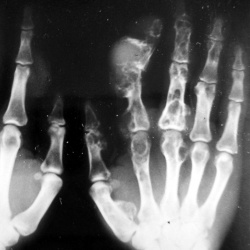

Пациент направлен на рентгенографию локтевого сустава. Была травма или не была не помнит. Пациент весьма пьющий, направлен хирургом с диагнозом "перелом". Рука в локтевом суставе полность не...